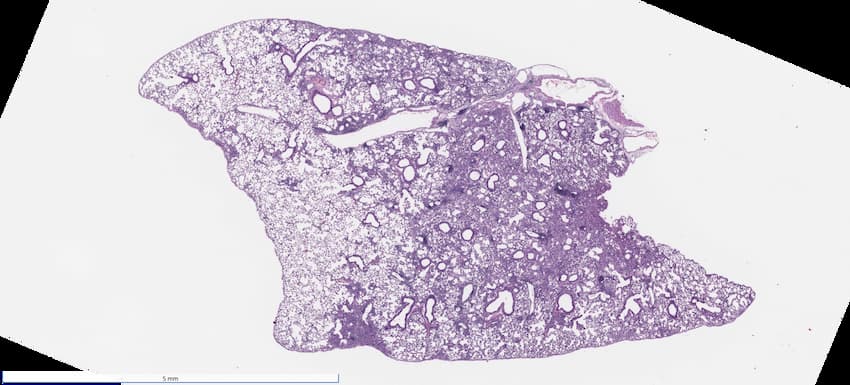

Every study to come through our lab starts with an H&E, so that our scientists and pathologists can assess your sample quality.